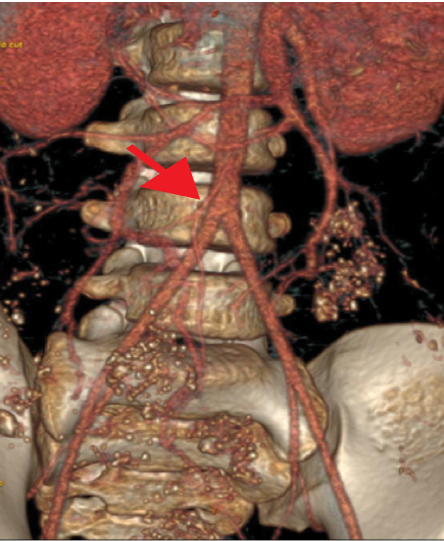

The contrast-enhanced computed tomography (CECT) abdomen findings were as follows: The D3 segment of the duodenum was seen to cross to the left side with the duodeno-jejunal junction in its expected location. The superior mesenteric arter-superior mesenteric vein (SMA-SMV) relationship was maintained with the SMV lying on the right side of SMA. The small bowel loops were predominantly on the left side of the abdomen, and the entire colonic loops were positioned on the right side of the abdomen [Figure 1]. The ileocecal junction (ICJ), cecum, and appendix were noted in the right lumbar region [Figure 2]. The inferior mesenteric artery was seen coursing to the right side of the midline, rather than its normal left-sided course [Figure 3]. A tubular cystic lesion was observed in relation to the small bowel loops on the left side of the abdomen [Figure 4]. Intrabdominal solid organs were essentially normal, with a normal situs.

Figure 3: 3D volume-rendered contrast-enhanced computed tomography arterial phase images showing the abnormal right-sided course of the inferior mesenteric artery (red arrow).